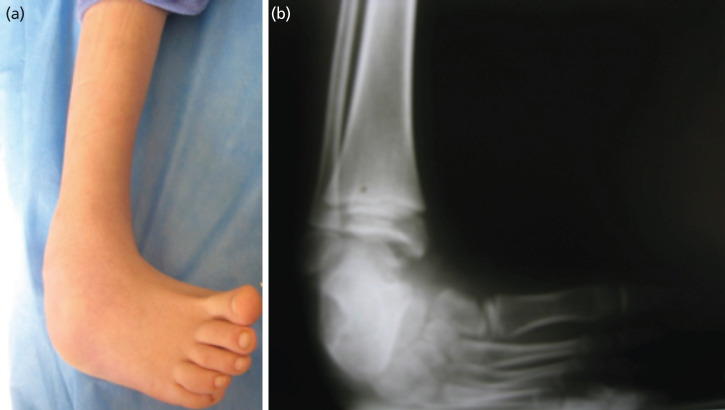

Materials and methods: In this cross-sectional study 47 patients (56 feet) between the ages of 5 and 10 years with clubfoot deformity were treated using the Ilizarov external fixator. Age, sex, type of deformity, and radiographic parameters were measured on foot radiographs. Also, the American Orthopaedic Foot and Ankle Society (AOFAS) score and the Dimeglio classification were recorded for each patient before and after treatment.

Results: The treatment was unilateral in 38 patients and bilateral in 9 patients. 39 patients (69.6%) were male, and 17 patients (30.4%) were female with a mean age of 7.86 ± 1.4 years. Plantar angles of ankle flexion and ankle flexion curve increased from 20.12±6.52 and -16.51±8.36 to 25.89±6.44 and 6.19±6.42, respectively. There was also an improvement in the talocalcaneal and tibiocalcaneal angles. Also, the angle between the first metatarsus and the talus in the front and side views improved (P<0.00). Additionally, the mean AOFAS score and Dimeglio classification significantly improved. Three cases were complicated with distal tibial physeal separation that were treated with additional open surgeries.

Conclusion: Ilizarov technique without osteotomies and soft tissue release could be considered a less invasive and successful method of treatment for neglected clubfoot deformity in patient five to ten years old that are not good candidate for Ponseti method.